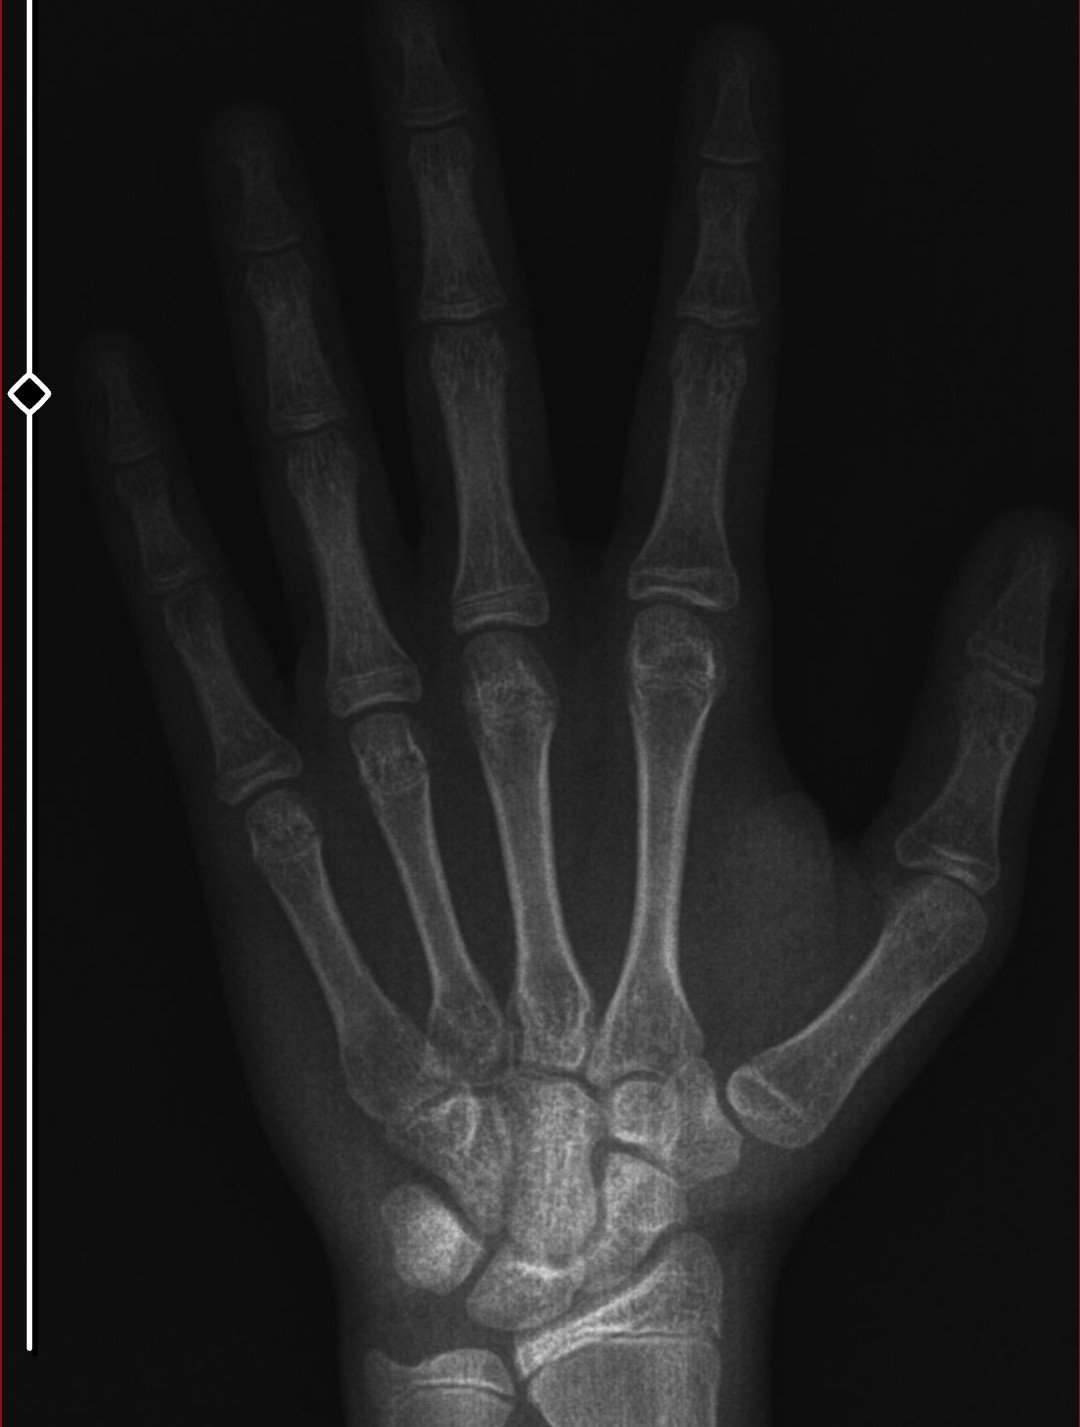

This is a x-ray from 3 months ago. I grew 1.5 centimeters from then im 177 now. I am 15 and almost 16. What do you think?

My doctor said that my bone age is way less than my real age. And she guarenteed that i would be 6'0+ (183) idk everyone tells a different thing. I analyzed mine and i think it was like 14.6 when i took that x-ray (i was 15.6 years old then)